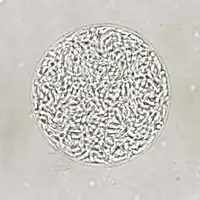

An unstained T. gondii tissue cyst, bradyzoites can be seen within

Bradyzoites

Bradyzoites are the slowly dividing stage of the parasite that make up tissue cysts. When an uninfected host consumes a tissue cyst, bradyzoites released from the cyst infect intestinal epithelial cells before converting to the proliferative tachyzoite stage.[30]: 359

T. gondii tissue cyst in a mouse brain, individual bradyzoites can be seen within

Following the initial period of infection characterized by tachyzoite proliferation throughout the body, pressure from the host's immune system causes T. gondii tachyzoites to convert into bradyzoites, the semidormant, slowly dividing cellular stage of the parasite.[38] Inside host cells, clusters of these bradyzoites are known as tissue cysts. The cyst wall is formed by the parasitophorous vacuole membrane.[30]: 343  Although bradyzoite-containing tissue cysts can form in virtually any organ, tissue cysts predominantly form and persist in the brain, the eyes, and striated muscle (including the heart).[30]: 343  However, specific tissue tropisms can vary between intermediate host species; in pigs, the majority of tissue cysts are found in muscle tissue, whereas in mice, the majority of cysts are found in the brain.[30]: 41

Cysts usually range in size between five and 50 µm in diameter,[39] (with 50 µm being about two-thirds the width of the average human hair).[40]